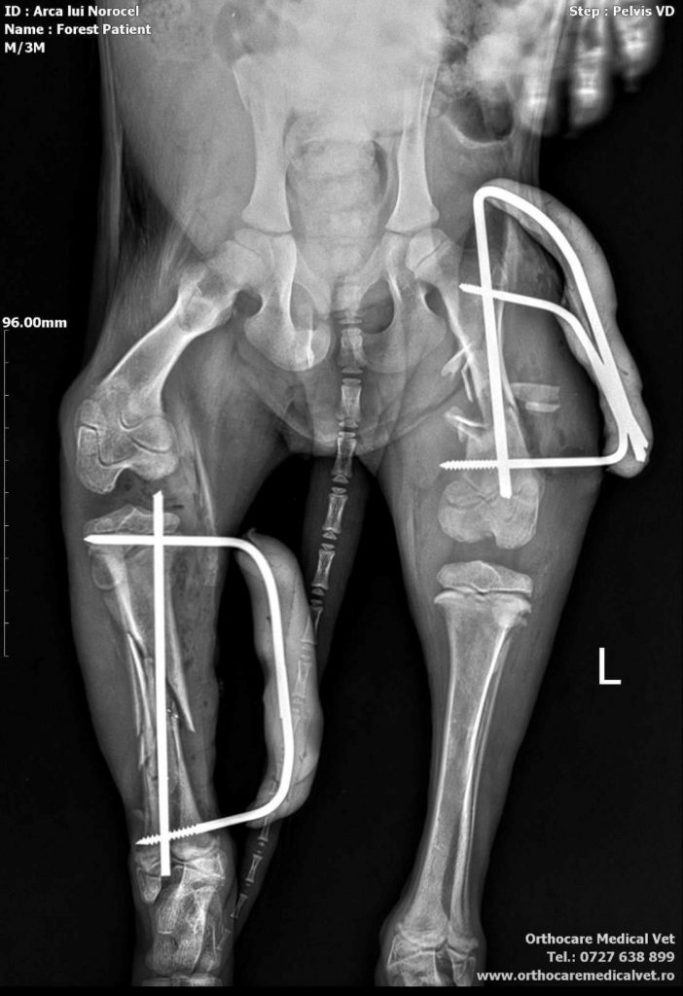

Forest, ein junger Rüde, wurde von einer Tierschützerin Christina auf der Straße gefunden – verletzt, vermutlich von einem Auto angefahren und einfach zurückgelassen. Doch dieser kleine Kerl hat einen unglaublichen Lebenswillen .Trotz seines schweren Starts ist Forest ein sehr freundlicher und zugewandter junger Hund.